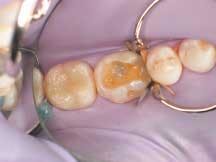

The teeth were etched using a total etch technique, applying etchant first on the enamel for three seconds, then carrying it onto the dentin area for an additional 12 seconds (for 15 seconds total etch) per tooth (Figure 2). Then the teeth were thoroughly rinsed and dried. A desensitizing agent (Systemp Desensitizer, Ivoclar Vivadent, Amherst, N.Y.) was then applied to the prepared dentition.

2